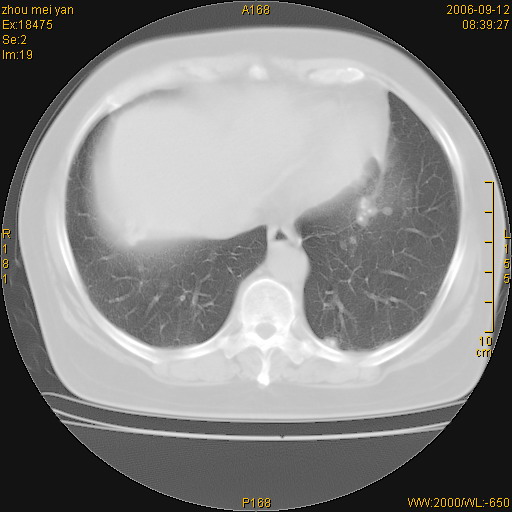

患者、女、55岁。因心率失常住院检查ct发现胸部多发结节。腹部b超肝、胆、胰、脾、肾、子宫附件未见异常。无结核病史,无粉尘接触史。请大家来会诊。谢谢!

病变位于胸膜,多发结节,边界清楚,内见小结节状钙化。其它未见异常。

双侧胸膜多发结节,形态不规则,边缘较清楚,每一个结节中心似乎都有钙化点的特征,与胸膜广基相切。临床无结核病史,无粉尘接触史。

影像表现十分有特点:双侧肋胸膜及膈胸膜广泛散在分布大小在2至6mm左右,较大病灶中心可见钙化。

考虑恶性胸膜间皮瘤可能性大,病灶位于胸膜,以宽基地与胸膜相连,呈结节样改变,部分病灶内可见点状钙化影。请各位老师多多指导!

双侧肋胸膜及膈胸膜广泛散在分布大小不等结节影,较大病灶中心可见钙化。